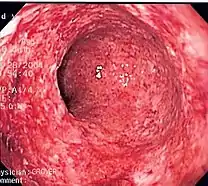

| The cardinal signs of inflammation include: pain, heat, redness, swelling, and loss of function. Some of these indicators can be seen here due to an allergic reaction. | |